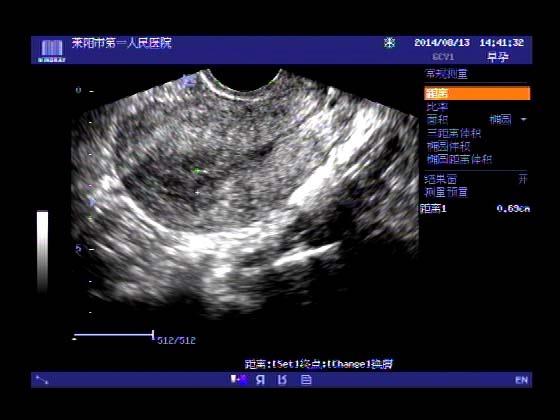

超声入门贴341:宫外孕(阴超的魅力)

女,32岁,停经15天,

一周前在上极医院检查:化验尿HCG阳性,血HCG400多,超声检查问见明显孕囊,让随访。

很典型,图像不错,阴超的优势!!